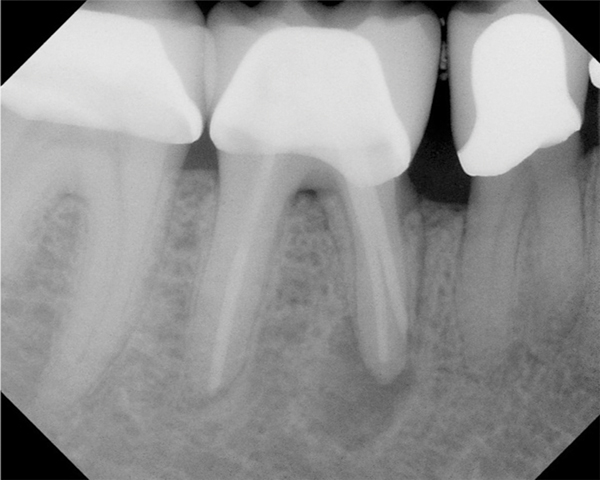

Figure 15. Preoperative radiograph. Courtesy of Dr. Sam Kratchman.

Figure 15

Figure 16. Post apicoectomy. Courtesy of Dr. Sam Kratchman.

Figure 16

Figure 17. Retropreps and isthus filled. Courtesy of Dr. Sam Kratchman.

Figure 17

Case 3: Apicoectomy and Retrofill

A patient presented with clinical symptoms and radiographic signs of post-endodontic disease (Figure 15). It was determined that the ledge on the mesial canals precluded retreatment and that an apicoectomy was to be performed. After locating the apicoectomy, it was possible to visualize both canals and an obvious isthmus between the two main canals (Figure 16). Retro-preparations were performed in the main canals, and the isthmus between them was grooved and the cavities filled with BC RRM-Putty (Figure 17). At the 20-month follow-up, the patient was asymptomatic and the radiograph showed complete healing (Figure 18).